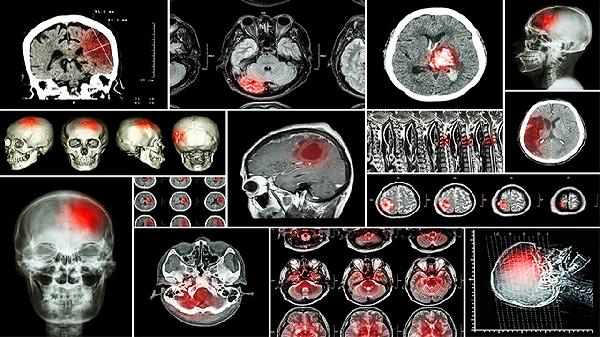

四、脑血管痉挛性头痛

由血压波动引发的脑血管痉挛性头痛患者,若头痛呈跳痛感、伴随眩晕恶心,且舌红苔黄脉弦数者适用。用药期间需记录头痛发作频率,避免与尼莫地平等钙拮抗剂联用。